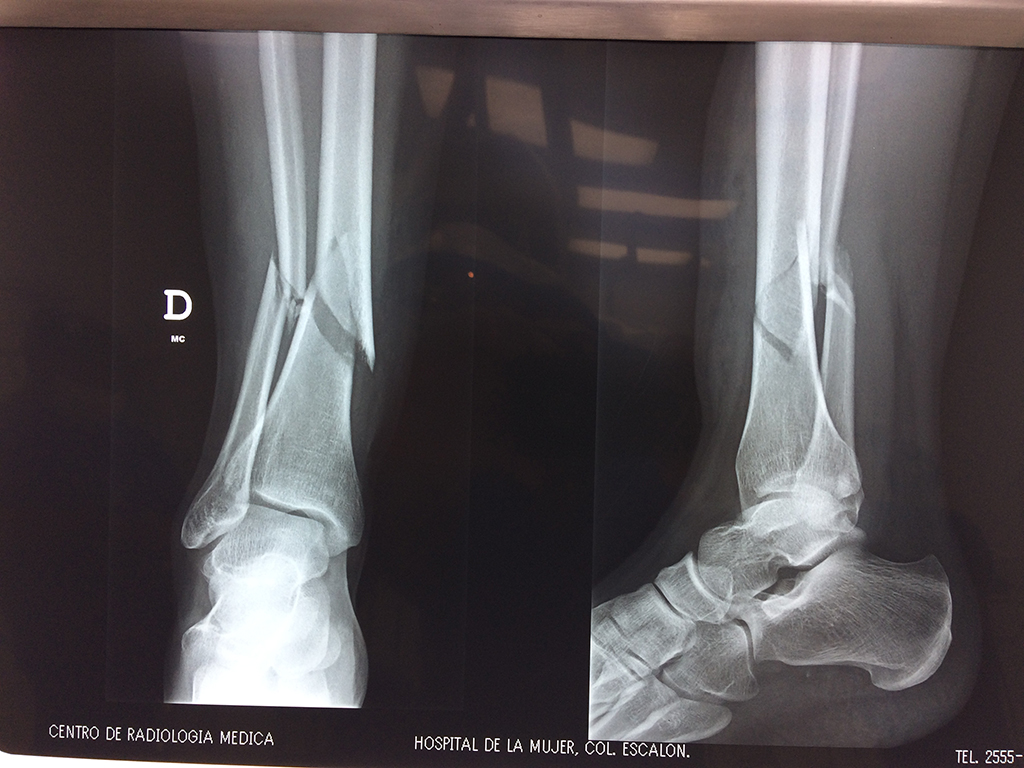

Húmero - Perone y Tibia

Aunque cada uno de estos huesos puede fracturarse por separado, normalmente la rotura es una lesión que se produce de forma conjunta

La mayor parte de las roturas implican a la parte proximal del hueso (parte del hueso próximo a la rodilla) o a la parte distal (parte del hueso cerca del tobillo).

Debido a la fina cobertura de piel que recubre la tibia y el peroné, las fracturas generalmente son abiertas, es decir, el hueso roto rasga la piel, atravesándola. Las fracturas de tibia y peroné generalmente se producen por un fuerte impacto o torsión.